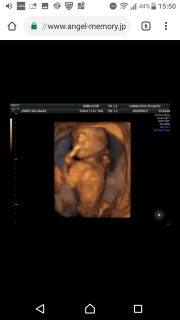

写真:16w1d:ゆっきぃさん:一卵性双子

*BPD3.3cm*FL2.0cm

週数ジャストの大きさだそうです(*˘︶˘*)

上の子が♂♂♀で今回のbabyは、、、なんか付いてそうですね〜!との事でした(*^^*)

前回の健診から1ヶ月たってて心配だったけど元気に動いてくれてちゃんと成長してくれててひと安心。 4D撮ってもらいました!! まだまだ骨だらけですがこれからしっかり育ってくれます様に。